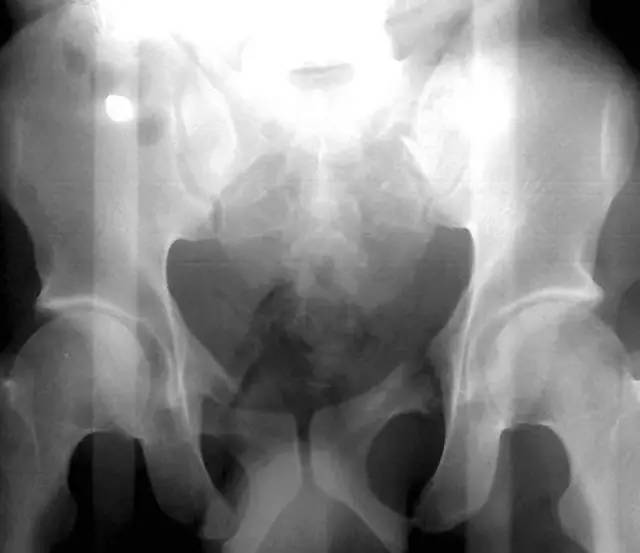

髋膝部骨折

1. Duverney 骨折

髂骨翼的骨折,但没有骨盆环的分离移位。

(来源:radiopaedia)

2. Malgaigne 骨折(bucket handle 骨折,即桶柄骨折)

不稳定性骨盆骨折伴有前方和后方的骨折线累及髋关节。

3. Straddle 骨折

双侧耻骨上下支骨折。

(来源:learning radiology)